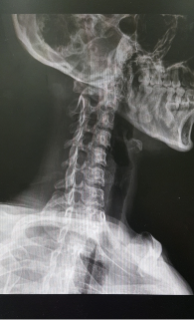

목 디스크는 목의 디스크(뼈 사이의 쿠션 역할을 하는 물질)가 손상되거나 파열되어 인접한 신경 및 조직에 압박을 주어 생기는 질환이다. 주로 긴 시간동안 고강도의 목 부담이나 부상 등이 원인이 되며, 목 아래쪽 통증, 근육약화, 두통, 어깨 및 팔에 통증, 미각 및 후각 상실 등의 증상이 나타난다. MRI 등의 영상진단을 통해 진단이 이루어지며, 보존적 치료와 수술적 치료가 가능하다. 초기 치료로는 안정 및 물리치료, 약물치료 등이 시행되고, 증상이 심한 경우 수술적 치료를 고려할 수 있다.

목 디스크는 경추부 디스크가 손상되어 디스크의 누출이나 폭발적인 파열 등의 문제가 발생하는 질환입니다. 이러한 문제로 인해 디스크가 인접한 신경에 압력을 가하게 되어, 강한 통증, 근육 경련, 저림 등의 증상이 나타납니다. 이 중에서 대표적인 증상은 목의 통증과 뻣뻣함, 두통, 어깨와 팔의 통증 및 저림 등이 있습니다. 또한, 목 디스크는 목을 움직일 때 통증이 증가하는 것이 특징입니다. 이러한 증상들은 주로 목 디스크가 경추부에서 발생할 때 나타나며, 경추부 디스크가 척추신경을 압박할 경우, 근육의 경련으로 인해 근육 긴장도 높아지는 경우가 많습니다.

또한, 목 디스크가 척추 신경근의 인대에 압박을 가할 때, 머리와 어깨가 뒤틀리는 증상이 나타날 수 있으며, 심한 경우에는 근육이 압박에 대한 보호 반사로 인해 경련이 발생하기도 합니다. 이 경우, 손가락이나 팔꿈치 같은 지점에서도 저림이 발생할 수 있으며, 목 디스크가 퇴행성 질환의 일종이기 때문에 증상은 서서히 나타나게 됩니다.

다만, 목 디스크 증상은 모든 환자에서 동일하지 않으며, 디스크의 위치, 크기, 손상 정도 등에 따라서 증상이 다르게 나타날 수 있습니다. 따라서, 정확한 진단과 치료가 필요합니다.